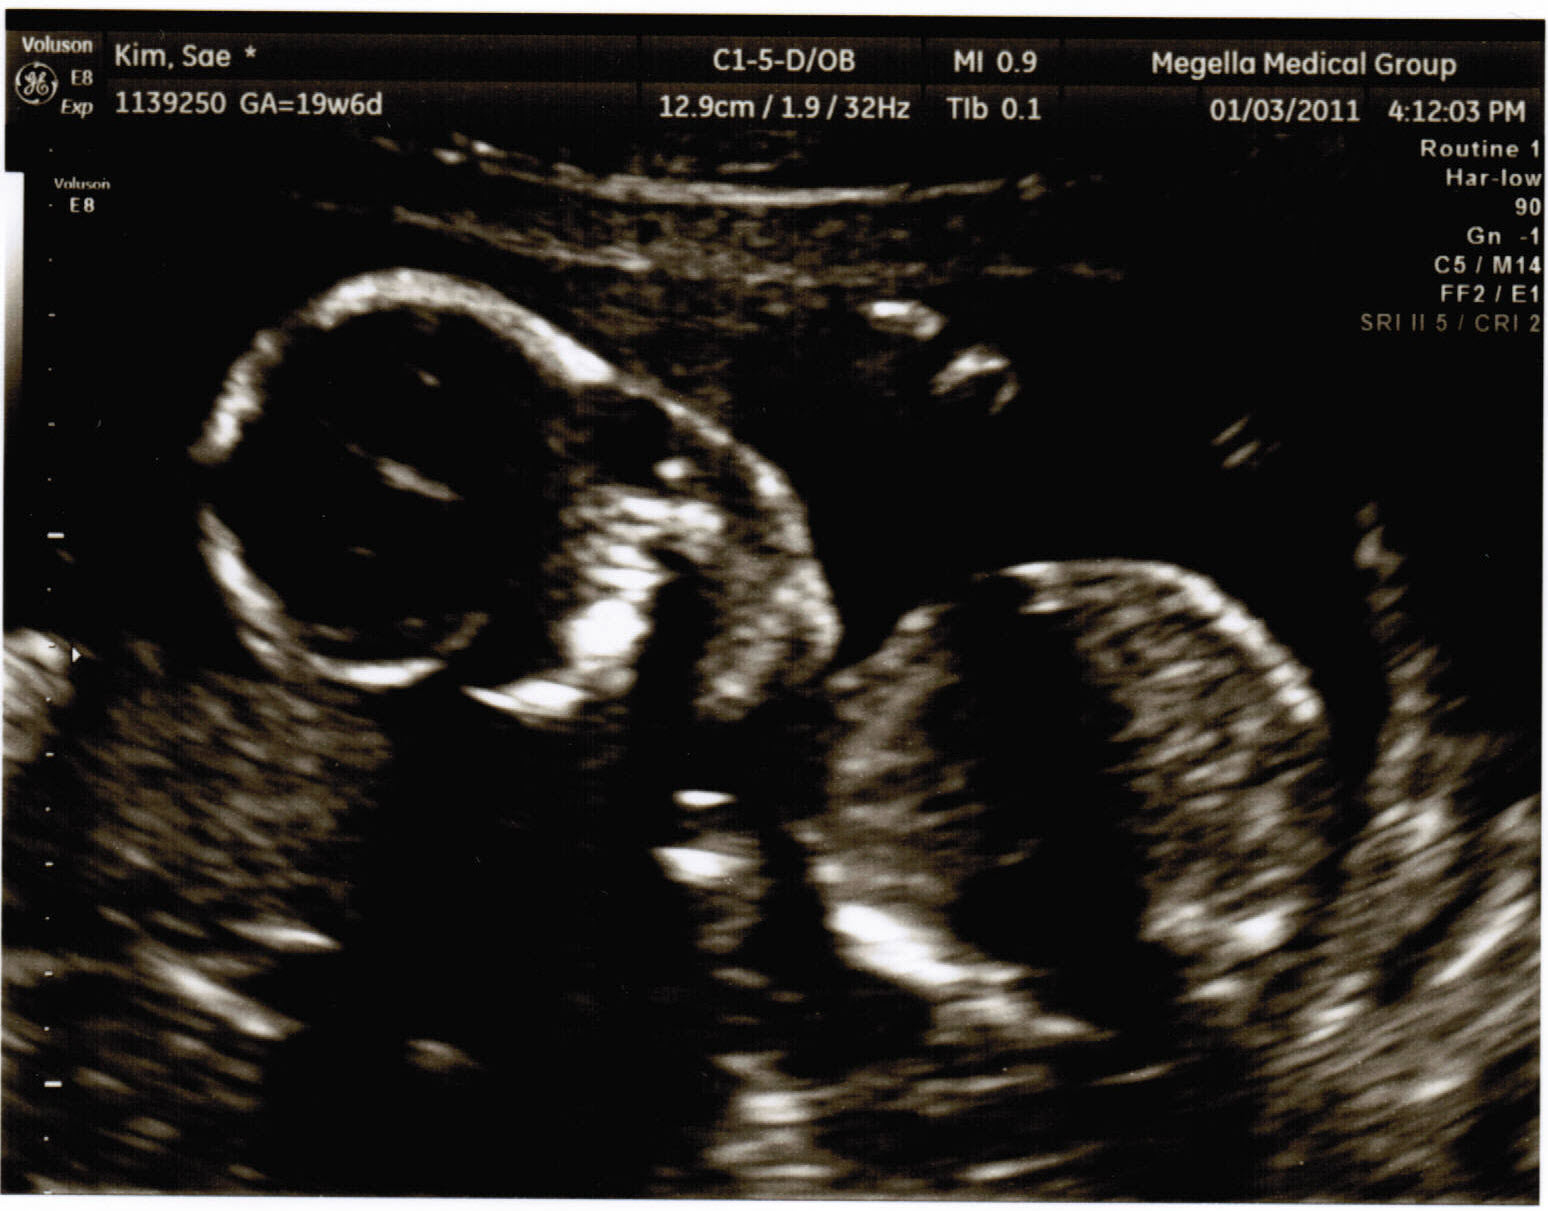

So this is it. The day we find out if it’s a boooooy or girrrrrrl!! Very interesting day, and I’ll tell you why. So we’re going through the whole sonogram process again checking the baby’s size, heart and movements. Yeah, yeah, yeah okay so i just wanted to say “come on lady just get to the point!” But anyway, as she moved into the lower Netherlands of the baby, i begin to stare hard, staring, trying to focus, then finally, i friggen see nothing. So i just look at the doctor, “weeeell?” All this while Lisa just lays there saying nothing. No expression. Any guy would be happy with a boy, as were the case with me, but i somewhat was convinced due to that fact of Lisa’s boasting of how a girl would be that much better and sweeter, swayed my intentions of somewhat wanting a girl a little more. Anyway, i’m still staring at the doctor, then at the screen, then back at the doctor, then she speaks “Okay so what you’re having is a ……… …… .. GIRL! Hearing the news I became sooooo happy, giddy, and couldn’t keep still. “A girl? Really? A girl? Yeeeeeees!” Okay, so all this time i was assuming that Lisa and I were on the same page and slightly leaning toward wanting to have a girl. But as I am celebrating I look over to her to expect a somewhat similar reaction, but, she just has no enthusiasm at all and is like ” a girl? really? a girl?